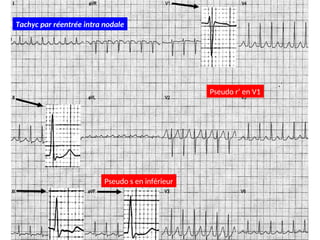

Pseudo r’ en V1

Pseudo s en inférieur

Tachyc par réentrée intra nodale

Pseudo r’ enV1 Pseudo s en inférieur Tachyc par réentrée intra nodale